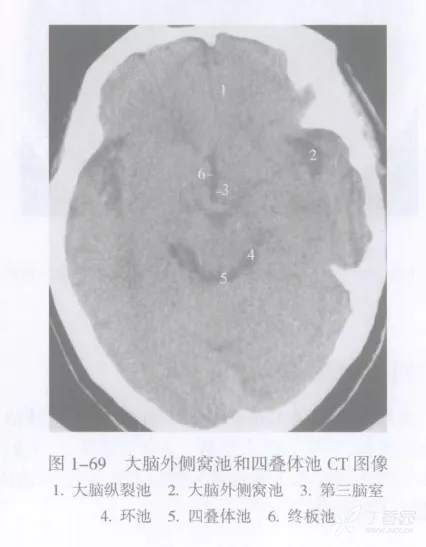

大脑外侧窝池

大脑外侧窝池 cistern of lateral fossa of cerebrum 又名侧裂池,位于大脑外侧窝内。

大脑外侧窝池在横断面上的典型表现呈横置的 “Y” 形,主干伸至岛叶表面即分为前后两支,前支较短伸向前内,后支较长伸向后方。

其中前后支又称为岛池,内侧对应的脑皮质即为脑岛叶。

大脑外侧窝池内有大脑中动脉的岛叶段和大脑中静脉经过大脑外侧窝池在青年人可以不明显,老年人常较清晰,脑萎缩者明显增宽。

四叠体池

四叠体池 quadrigeminal corpus cistern 又称上池 superior cistern ,居中脑四叠体后面与小脑蚓部前缘之间,两端向外连于环池翼部,向前外通环池本部。四叠体池和环池位于小脑幕切迹内,幕上或幕下的病变可经这些脑池延伸。例如,小脑幕切迹疝可使这些脑池变窄或消失。